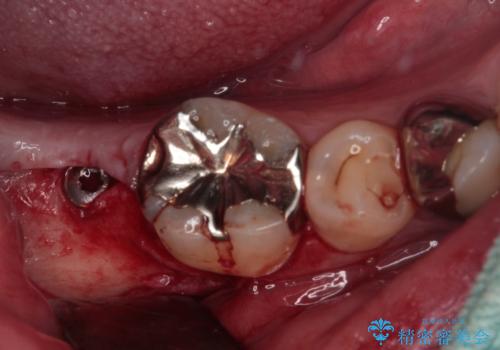

- 下顎左右の奥歯を治療途中で放置してしまっているとのことで来院された患者様です。

欠損部はインプラントによる補綴治療を、土台の外れてしまった歯は、根管治療を行った上で、補綴治療を行うこととしました。

骨格的に下顎が大きく上顎が小さいため、奥歯に力の負担のかかりやすい咬み合わせであるので、治療後は睡眠時にマウスピースを装着することで、セラミッククラウンやインプラント、治療をしたご自身の歯が長持ちするよう指導しています。